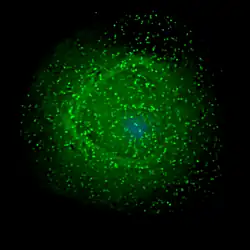

O VIH infecta células vitais no sistema imunitário, como os linfócitos T auxiliares CD4+, macrófagos e células dendríticas.[4] A infeção por VIH provoca a diminuição do número linfócitos T CD4+ através de diversos mecanismos, entre os quais a apoptose de células espectadoras,[5] a morte viral direta de células infectadas, e morte de linfócitos T CD4+ através de linfócitos T citotóxicos CD8 que reconhecem as células infectadas.[6] Quando o número de linfócitos T CD4+ desce abaixo do limiar aceitável, o corpo perde a imunidade mediada por células e torna-se progressivamente mais suscetível a infeções oportunistas.

O termo tropismo viral refere-se ao tipo de células que determinado vírus infeta. O VIH pode infetar diversas células imunitárias, como os linfócitos T CD4+, macrófagos e microgliócitos. A entrada do VIH-1 nos macrófagos e nos linfócitos CD4+ é mediada através da interação das glicoproteínas do envelope do virião (gp120) com a molécula CD4 nas células-alvo, e ainda através de co-recetores de quimiocina.[24]

As cadeias do VIH-1 que afectam os macrófagos (M-trópicas) usam os co-recetores de quimiocina CCR5 para entrar, sendo assim capazes de se replicarem em macrófagos e linfócitos T CD4+.[31] Este co-recetor CCR5 é usado por praticamente todos os tipos primários de VIH-1, independentemente do seu subtipo genético. Assim, os macrófagos desempenham um papel essencial em vários aspetos fundamentais da infeção por VIH, aparentando ser as primeiras células a ser infetadas e talvez a fonte de produção de VIH a partir do momento em que o doente perde as células CD4. Em amígdalas e adenoides de doentes infetados com VIH, os macrófagos fundem-se em células de grandes dimensões e vários núcleos que produzem grandes quantidades de partículas virais. As cadeias T-trópicas replicam-se tanto em linfócitos T CD4+ como em macrófagos e usam para entrar o co-recetor de quimioquina CXCR4.[31][32][33] Pensa-se que as cadeias VIH-1 de tropismo duplo sejam cadeias de VIH-1 em transição, e portanto capazes de usar como co-recetores de entrada tanto o CCR5 como o CXCR4. A quimioquina-alfa SDF-1, um ligante do CXCR4, suprime a replicação dos tipos T-trópicos. Consegue-o através da infra-regulação da expressão do CXCR4 na superfície destas células. O VIH que usa apenas o co-recetor CCR5 é denominado R5; o que usa apenas o CXCR4 é denominado X4; e o que usa ambos é denominado X4R5. No entanto, o uso do co-recetor por si só não explica o tropismo viral, já que nem todos os vírus R5 são capazes de usar o CCR5 em macrófagos de modo a dar origem a uma infeção bem sucedida e o VIH pode também infetar um subtipo de células dendríticas mieloides, que provavelmente constituem uma reserva que mantém a infeção quando a contagem de células CD4+ desce para níveis extremamente baixos.[31][34] Algumas pessoas são resistentes a determinadas estirpes de VIH.Por exemplo, pessoas com a mutação CCR5-Δ32 são resistentes a infeções com o vírus R5, uma vez que a mutação impede o VIH de se ligar ao seu co-recetor, reduzindo a sua capacidade de infetar células-alvo.[35]